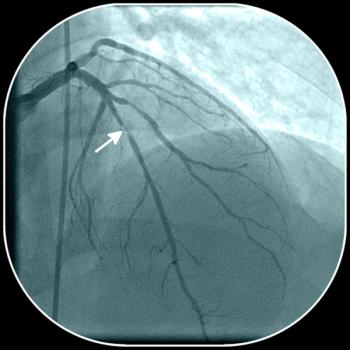

Antiretroviral drug regimens have been implicated as factors in the increased risk of coronary artery disease and myocardial infarction in those with HIV infection. Here: practical measures for prevention and screening.